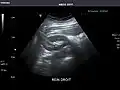

Renal ultrasonography

Ultrasonography of the kidneys is essential in the diagnosis and management of kidney-related diseases. The kidneys are easily examined, and most pathological changes in the kidneys are distinguishable with ultrasound.[7]

Kidneys: Right and left kidneys measure 11.5 cm and 12 cm in length respectively. No hydronephrosis. Small left lower pole kidney cyst.

Right kidney -